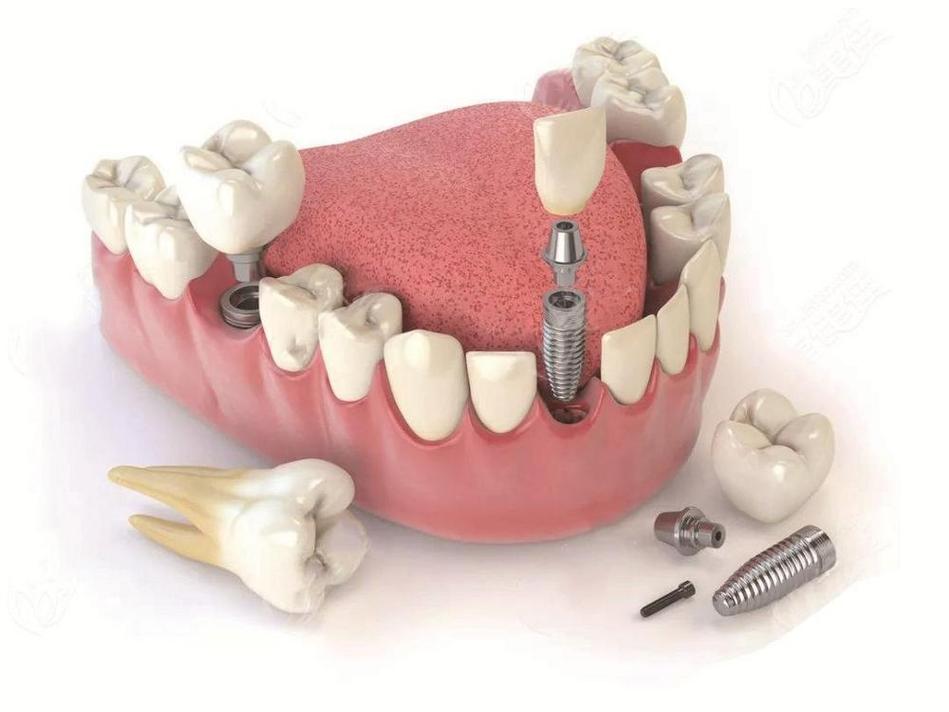

在种植体设计上,卡瓦采用锥形螺纹和渐进式螺纹结构,这种设计能在植入时实现自攻效应,减少对骨组织的损伤,同时通过分散咬合力降低种植体周围骨吸收的风险,种植体内部的平台转移(platform switch)设计,将基台连接平台内移,使边缘骨与种植体界面远离微间隙,有效预防细菌侵入和边缘骨吸收,长期稳定性更佳,卡瓦种植系统提供多种直径和长度的种植体型号,针对不同骨质类型(如Ⅰ类骨、Ⅳ类骨)和临床病例(如即刻种植、即刻负重)均有适配方案,满足复杂口腔修复需求。

- 基台安装与牙冠修复:骨结合完成后(3-6个月),安装个性化基台,并通过CAD/CAM技术制作全瓷牙冠,最终实现种植体的功能与美学重建。